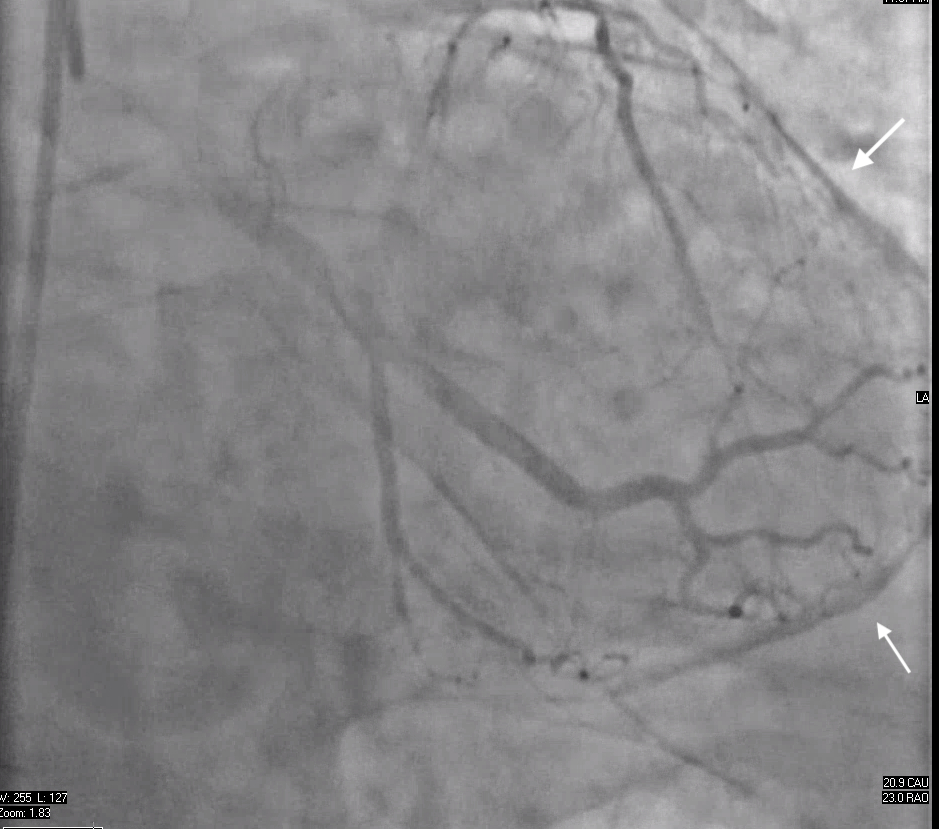

Initial evaluation in 2022 showed preserved left ventricular ejection fraction and no pericardial abnormalities on transthoracic echocardiogram. Myocardial perfusion SPECT revealed a mild right coronary artery perfusion defect. EKG showed right bundle branch block with nonspecific ST-T changes. In February 2024, left heart catheterization revealed mild coronary artery disease and incidental pericardial calcifications. By June 2024, CT angiography confirmed diffuse pericardial thickening and dense calcifications around the left ventricular apex, consistent with prior pericarditis.

Right heart catheterization in July 2024 demonstrated equalization of diastolic pressures (Right Atrium: 25 mmHg, Right Ventricular End Diastolic Pressure: 24 mmHg, Pulmonary Capillary Wedge Pressure: 24 mmHg, Left Ventricular End Diastolic Pressure: 24–25 mmHg), reduced cardiac output (1.6 L/min), low cardiac index (1.7 L/min/m2), and mildly elevated Pulmonary Vascular Resistance (3.2 Wood units), confirming CP. The patient underwent pericardiectomy without cardiopulmonary bypass in August 2024. Pathology showed pericardial calcifications and chronic inflammation. Postoperatively, the patient reported improved exercise tolerance and resolution of symptoms.